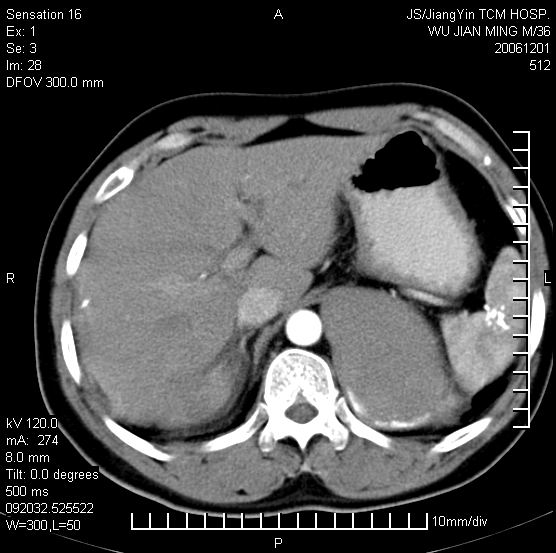

以下是引用dyqct在2006-12-1 21:17:00的发言:[br]左心缘旁及后肋膈窦区见巨大椭圆形混杂密度肿块,周围见大小不等斑片状钙化,内部无强化,周围包膜轻度强化,心脏明显受压变形,即明显占位效应,肿块广基与心包、膈相连。肝、脾内、肝门见多数小结节状钙化影。[br]考虑:1、左心缘旁及后肋膈窦区慢性包裹性胸膜炎(结核性);[br] 2、肝、脾及肝门淋巴结核已钙化。[br]

以下是引用zrs在2006-12-2 17:28:00的发言:[br]肺内、肝脾内虽有钙化,但不支持结核性胸胸膜炎包裹,而支持寄生虫感染![br][br]

以下是引用zyx168在2006-12-2 10:10:00的发言:[br][br]肝脾肺内多发钙化灶